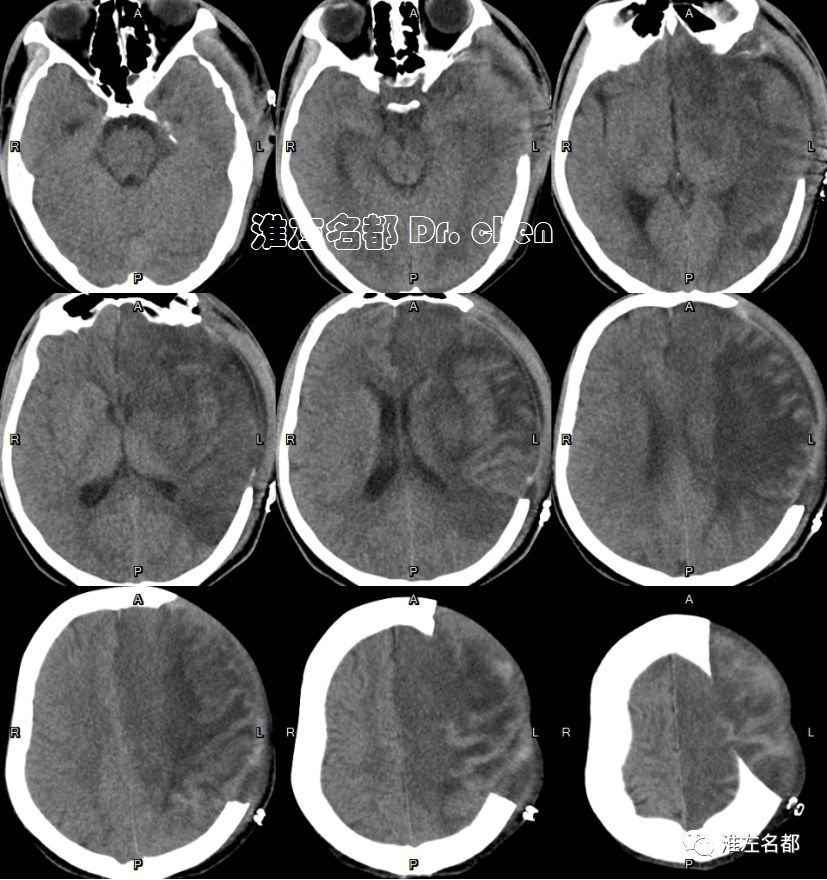

△头颅CT平扫:左侧半球大范围低密度,灰白质分界消失,脑沟受压变小-消失;左侧大脑中动脉区ASPECT-2。

△颅脑CT平扫+增强:左侧基底节区和部分额叶呈稍高密度,左侧前循环血流通畅;左侧半球肿胀明显,脑室、脑沟和脑池受压,中线结构向右侧显著移位。

△头颅CT平扫:左侧去骨瓣减压术后,左侧半球仍有肿胀,中线结构移位较前稍改善。

△头颅CT:左侧去骨瓣减压术后,中线结构居中,侧脑室受压较前改善。

△头颅CT平扫:左侧去骨瓣减压术后,左侧半球大面积梗死组织坏死软化,左侧侧脑室扩大。

△头颅CT平扫:左侧去骨瓣减压术后,左侧半球大面积陈旧性梗死软化灶,左侧侧脑室扩大。

△头颅CT平扫:左侧半球大面积陈旧性梗死软化灶,左侧颅骨修补术后。